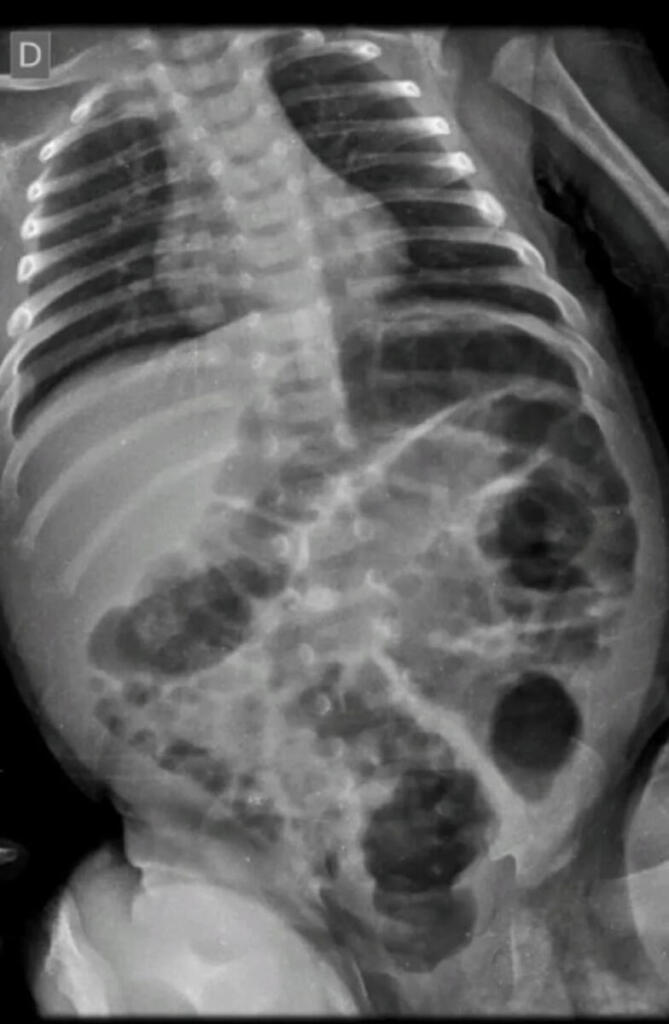

Exames de raio-X mostraram que, além de hematomas e escoriações pelo corpo, o bebê também sofreu lesões ósseas em uma das tíbias, em um antebraço e também nas costelas. O laudo médico apontou ainda que os ferimentos expuseram o bebê a risco de vida.